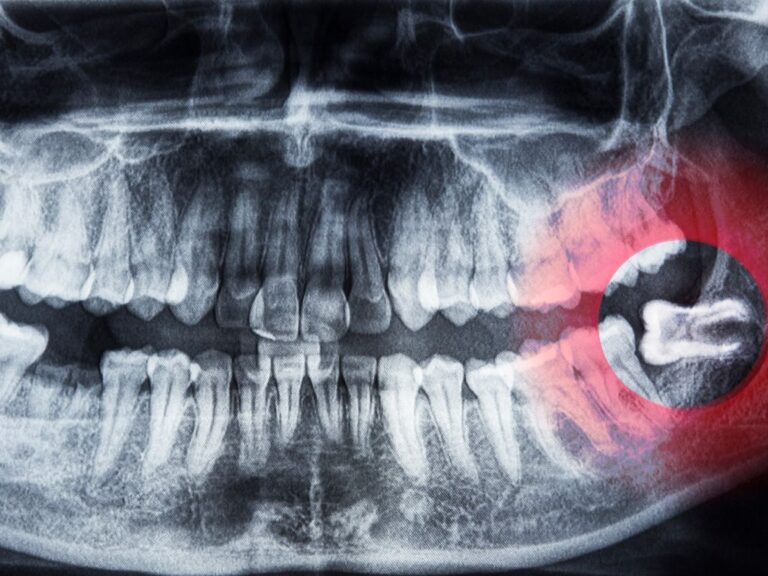

Czy trzeba usuwać ósemki jeśli nie bolą? To pytanie pada często, bo ząb mądrości potrafi